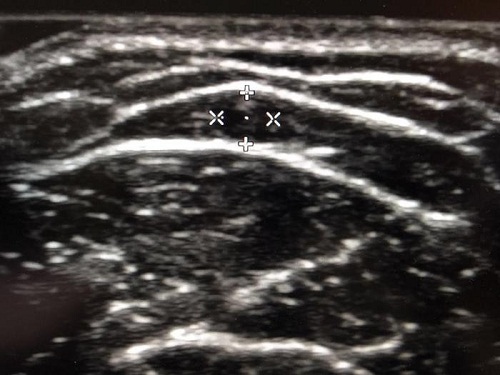

术前超声检查头静脉,精准定位,图示所示头静脉直径约3mm

术前的超声评估是非常重要的,通过术前超声评估我们可以判断血管内适不适合植入输液港,比如血管内有血栓、血管纤细、管腔的狭窄都不适合植入。超声确认血管条件良好,同时可以将血管走行区标记出来,精准定位,方便术中寻找到该血管植入输液港,可以将伤口做到最小,避免损伤周围组织,缩短了手术时间。输液港导管进入血管以后末端需要依靠X线定位,调整到最佳位置。以上的措施都是精准植入输液港必要的手段,顺应了“保护血管”的人性化先进理念,导管与头静脉固定避免了移位的发生。术前超声血管评估和定位、术中透视下精准导管末端定位和保护血管理念、预防及处理导管相关血栓形成并发症是血管外科医生的独有技能。